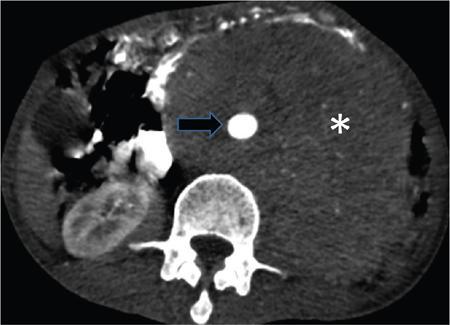

Fig. 10.17.1.8 Contrast-enhanced axial (A–D) and sagittal CT (E) sections in a case of a pelvic retroperitoneal haematoma. The right kidney appears bulky with perinephric fat stranding. Active leak of contrast from the right external iliac artery is seen on the arterial phase (blue arrow in A) with a resultant large haematoma (asterisks in A–D). Superiorly, it extends along the combined interfascial plane into the perirenal space (blue arrow in E) as well as along the retromesenteric (blue arrows in C and D) and retrorenal planes (asterisk in C). Medially the haematoma tracks into the central compartment (asterisk in D) via the perirenal space.